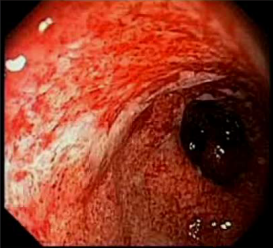

How do you confirm this diagnosis?

This is eosinophilic esophagitis, note the eosinophilic microabscesses on the esophageal wall and concentric rings. This is diagnosed by biopsy w/15-20 Eos per high power field.

How do patients with EoE typically present first and how do you first manage them?

1st: intermittent dysphagia. Treat w/PPI, then if that doesn’t work you treat with topical steroids.